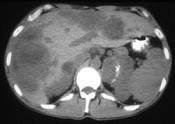

- 多项选择题男,37岁, 阵发性高血压1月余,请结合所提供图像, 选择最佳答案 ( )

A、左侧肾上腺癌

B、左侧恶性嗜铬细胞瘤

C、左侧肾上腺转移瘤

D、肝转移瘤

E、原发性肝癌